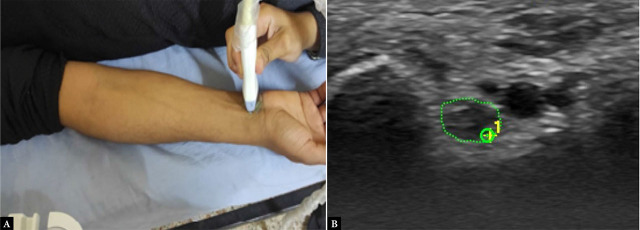

Aim of the study: This study seeks to evaluate the effectiveness of ultrasound measurements of the ulnar nerve cross-sectional area in comparison to electrodiagnostic tests for identifying ulnar nerve entrapment at the elbow in rheumatoid arthritis.

Patients and methods: This study was designed as a cross-sectional observational analysis involving 90 individuals, divided into three groups: Group A consisted of 30 individuals diagnosed with rheumatoid arthritis without clinical signs of ulnar neuropathy at the elbow; Group B included 30 individuals with rheumatoid arthritis exhibiting clinical indicators of ulnar neuropathy at the elbow; and Group C comprised 30 healthy controls. Each participant underwent a thorough medical history assessment, along with both clinical and neurological evaluations. Additionally, ultrasound and electrophysiological assessments of the ulnar nerve were performed.

Results: There was no significant demographic difference between the groups, except for age, which was notably lower in Group A compared to Group B. Additionally, abnormalities in nerve conduction studies and cross-sectional area were found to be significantly greater in Group B (p <0.0001). The cross-sectional area demonstrated diagnostic accuracy rates of 52.22%, 62.22%, and 78.89% for identifying ulnar neuropathy at Guyon's canal, the medial epicondyle, and based on the elbow-to-wrist ratio, respectively.

Conclusion: Ultrasonography exhibits high diagnostic accuracy, especially with the cross-sectional area at the medial epicondyle and the elbow-to-wrist cross-sectional area ratio serving as important indicators for ulnar nerve entrapment in patients with rheumatoid arthritis.